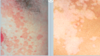

Identifiez

Pityriasis versicolore – variante hypopigmentée

Identifiez

Pityriasis versicolore hypopigmenté en gouttes